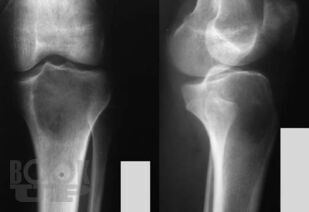

Рентгенологические и ультразвуковые исследования при заболеваниях суставов

Семизоров А. Н. Рентгенологические и ультразвуковые исследования при заболеваниях суставов : Пособие для врачей / А. Н. Семизоров, С. В. Романов. - М. : Видар-М, 2008. - 216 c. - ISBN 9785884291140. - Текст : электронный // ЭБС "Букап" : [сайт]. - URL : https://www.books-up.ru/ru/book/rentgenologicheskie-i-ultrazvukovye-issledovaniya-pri-zabolevaniyah-sustavov-9194384/ (дата обращения: 23.05.2026). - Режим доступа : по подписке.

Предлагаемая книга является дальнейшим развитием вышедшего ранее пособия «Ретнгенологическое и ультразвуковое исследование при заболеваниях

суставов».

Иллюстративная часть материала дополнена рентгенограммами, расширен

и углублен текст. В книге изложены основы рентгенологической и ультразвуко

вой диагностики дегенеративнодистрофических, воспалительных и других

заболеваний суставов. Представлены особенности диагностики при наиболее

часто встречающихся в клинической практике заболеваниях суставов.

Пособие рассчитано на рентгенологов, врачей УЗИ, ортопедов и врачей других специальностей.